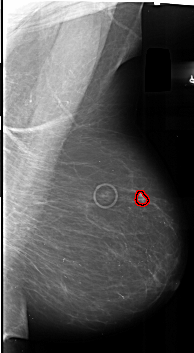

A_1010_1.RIGHT_MLO

RIGHT_MLO LINES 6001 PIXELS_PER_LINE 3286 BITS_PER_PIXEL 16 RESOLUTION 42 OVERLAY

FILE: A_1010_1.RIGHT_MLO.OVERLAY

TOTAL_ABNORMALITIES 1

ABNORMALITY 1

LESION_TYPE MASS SHAPE IRREGULAR MARGINS SPICULATED

ASSESSMENT 5

SUBTLETY 4

PATHOLOGY MALIGNANT

TOTAL_OUTLINES 1

BOUNDARY